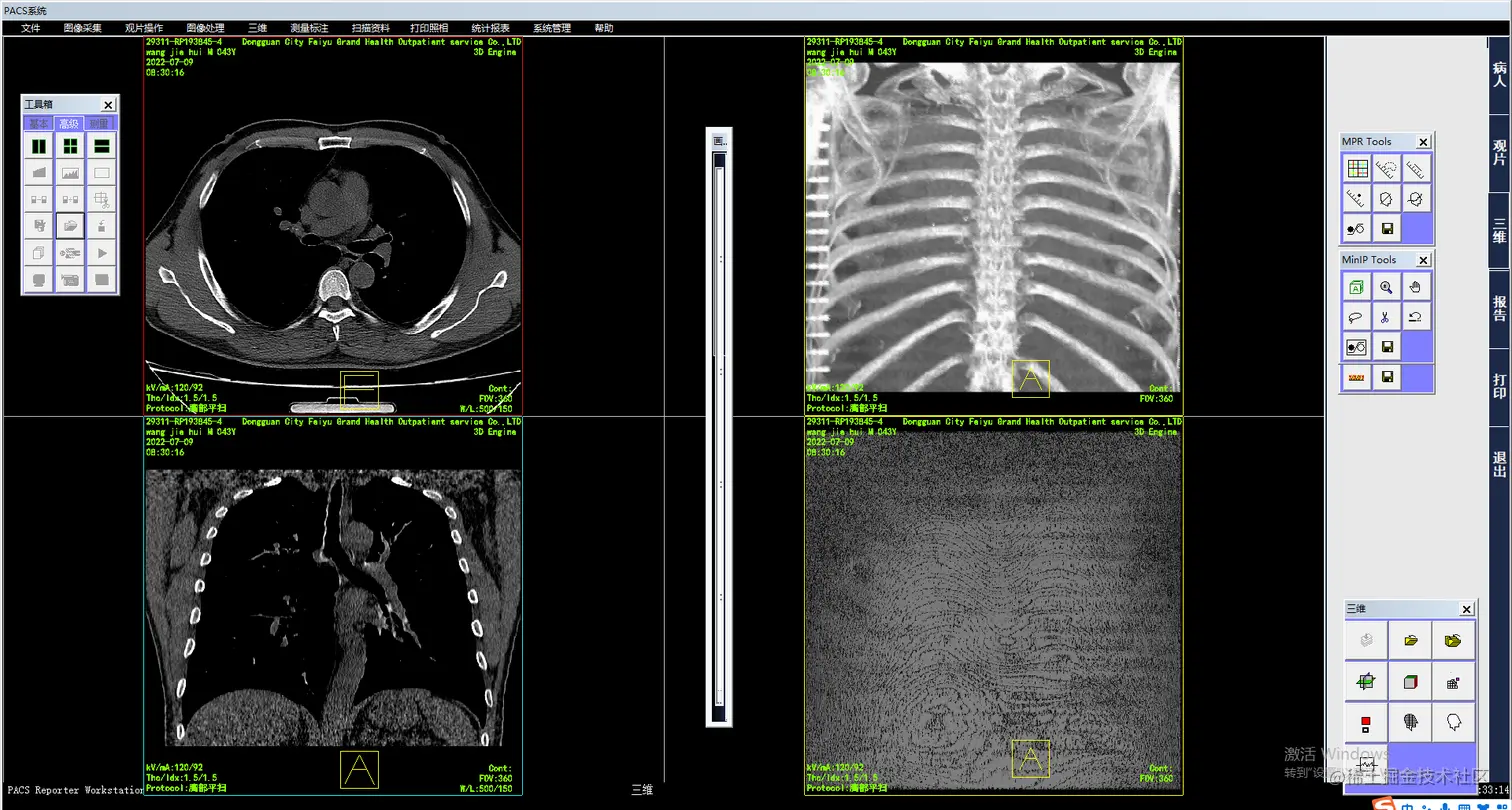

医院管理系统PACS源码带3D重建和还原

CT三维重建主要包含以下基本后处理方法:

多层面重建(MPR) 最大密度投影(MIP) 最小密度投影(MinIP) 表面阴影遮盖(SSD) 容积漫游技术(VRT) 虚拟内镜技术(VE)

1、MPR    MPR(Multi-Planar Reformatting),多平面重建,是将扫描范围内所有的轴位图像叠加起来再对某些标线标定的重组线所指定的组织进行冠状、矢状位、任意角度斜位图像重组。MPR适用于任一平面的结构成像,以任意角度观察正常组织器官或病变,可以显示腔性结构的横截面以观察腔隙的狭窄程度、评价血管受侵情况、真实地反映器官间的位置关系等。

PACS系统是Picture Archiving and Communication Systems的缩写,意为影像归档和通信系统。它是应用在医院影像科室的系统,主要的任务就是把日常产生的各种医学影像(包括核磁,CT,超声,各种X光机,各种红外仪、显微仪等设备产生的图像)通过各种接口(模拟,DICOM,网络)以数字化的方式海量保存起来,当需要的时候在一定的授权下能够很快的调回使用,同时增加一些辅助诊断管理功能。它在各种影像设备间传输数据和组织存储数据具有重要作用。

• 提供多种高级影像后处理功能:(包括三维多平面重建、三维容积重建、三维表面重建、三维虚拟内窥镜、最大/小密度投影、心脏动脉钙化分析);